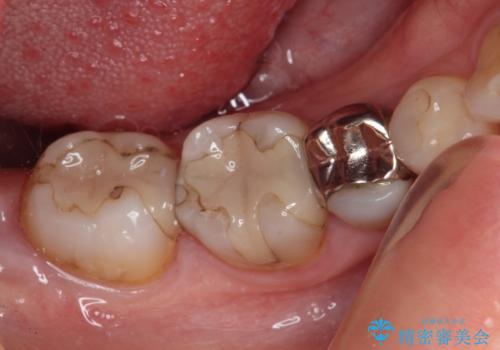

- 奥歯の虫歯を心配して来院した患者様です。

レントゲン写真から、以前治療した詰め物の下に虫歯があることがわかりました。

精度が高く、虫歯の再発リスクの低いゴールドインレーで治療を行うこととしました。